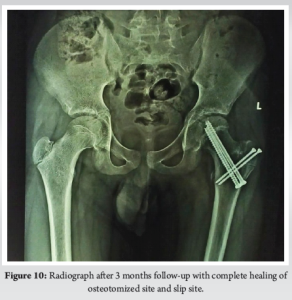

A 15-year-old boy with body mass index (BMI)-18.6 kg/m2 presented to the emergency department with acute left hip pain and inability to bear weight. The pain began after a minor stumble while playing at his school, though he denied any significant trauma. He was initially able to weight bear but gradually pain progressed leading to difficulty in walking and unable to weight bear over the past 24 h. His medical history was unremarkable. His family history was negative for hip disorders, early-onset osteoarthritis, or metabolic conditions. Examination revealed lower limb in flexion, shortened and externally rotated with diffuse tenderness over hip region. Radiography showing widening and irregularity of the left physeal plate, posterior displacement of the femoral epiphysis relative to the femoral neck (Fig. 1] and Klein’s line failed to intersect the epiphysis (positive Trethowan’s sign) (Fig. 2a). Based on clinical presentation and imaging, the patient was diagnosed with: Unstable, severe SCFE (Fig. 2b) (Southwick angle >50°), high risk for osteonecrosis due to inability to bear weight. Given the severity of displacement and instability, MDP was selected over traditional ISP to restore hip anatomy and preserve femoral head vascularity. Patient underwent the MDP through a Ganz surgical hip dislocation approach, performed under general anesthesia. A straight digastric osteotomy of the greater trochanter was performed leaving the most posterior fibers of gluteus medius tendon intact (Fig. 3). This did not potentially endanger the deep branch of the medial femoral circumflex artery. Mobilization of the trochanteric fragment together with the vastus, gluteus minimus, and medius muscles was done ventrally to expose the capsule. A Z-shaped capsulotomy was performed providing access to the displaced epiphysis (Fig. 4). Femoral epiphysis was temporarily pinned with 2 mm Kirschner wires. The viability of femoral epiphysis was ensured by drilling of the femoral head. Dislocation of femoral head was done by flexion and external rotation and placement in a sterile bag by the side of operating table. Full inspection of acetabulum was done to see any corresponding chondral damage. After relocating the head, retinacular soft-tissue flap containing deep branch of medial femoral circumflex artery, the periosteum, the piriformis muscle, part of the posterior capsule, and the short external rotators was developed (Fig. 5). Distally, the flap was mobilized till the level of the lesser trochanter which reduced the tension from the retinacular vessels. Complete epiphyseal mobilization (Fig. 6) and carefully separating the femoral epiphysis from the posteriorly displaced metaphysis was facilitated by external rotation. The excess callus formation of the metaphysis which was seen was resected until a spherical surface of neck became reapparent. The epiphysis was then reduced manually on the metaphyseal stump (Fig. 6). A 3.0 mm Kirschner wire was placed anterograde for temporary reduction and checked under fluoroscopy for capital realignment. Internal fixation was done using one fully (75 mm) and one partially (80 mm) threaded 6.5 mm cannulated cancellous screws for stable fixation (Fig. 7). Retinacular soft-tissue flap was reattached back with tension free sutures. Similarly, capsule was closed without tension. Osteotomy site was fixed at the end with two 3.5 mm cortical screws. In immediate post-operative period (Fig. 8), the patient was kept non-weight-bearing for 6 weeks with strict activity modification, physical therapy initiated with passive range-of-motion (ROM) exercises at post-operative day 2 to prevent stiffness, pain was well controlled with non-steroidal anti-inflammatory drugs, and no early post-operative complications were noted. 6 weeks post-operative, radiographs showed stable fixation with no further slip progression, early signs of physeal healing were observed. Patient regained near full near-full ROM with no significant pain (Fig. 9). Three months post-operative (Fig. 10), the patient transitioned to full weight-bearing. At present, the patient is 4 months post-operative and able to do regular activities without restriction. Radiographs showed complete healing of the osteotomy site No clinical or radiographic evidence of FAI or chondrolysis were found.